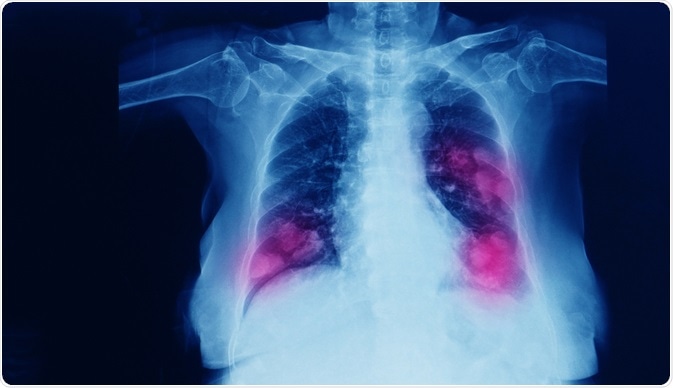

Primary Lung Cancer

Image Credit: Yok_onepiece/Shutterstock.com